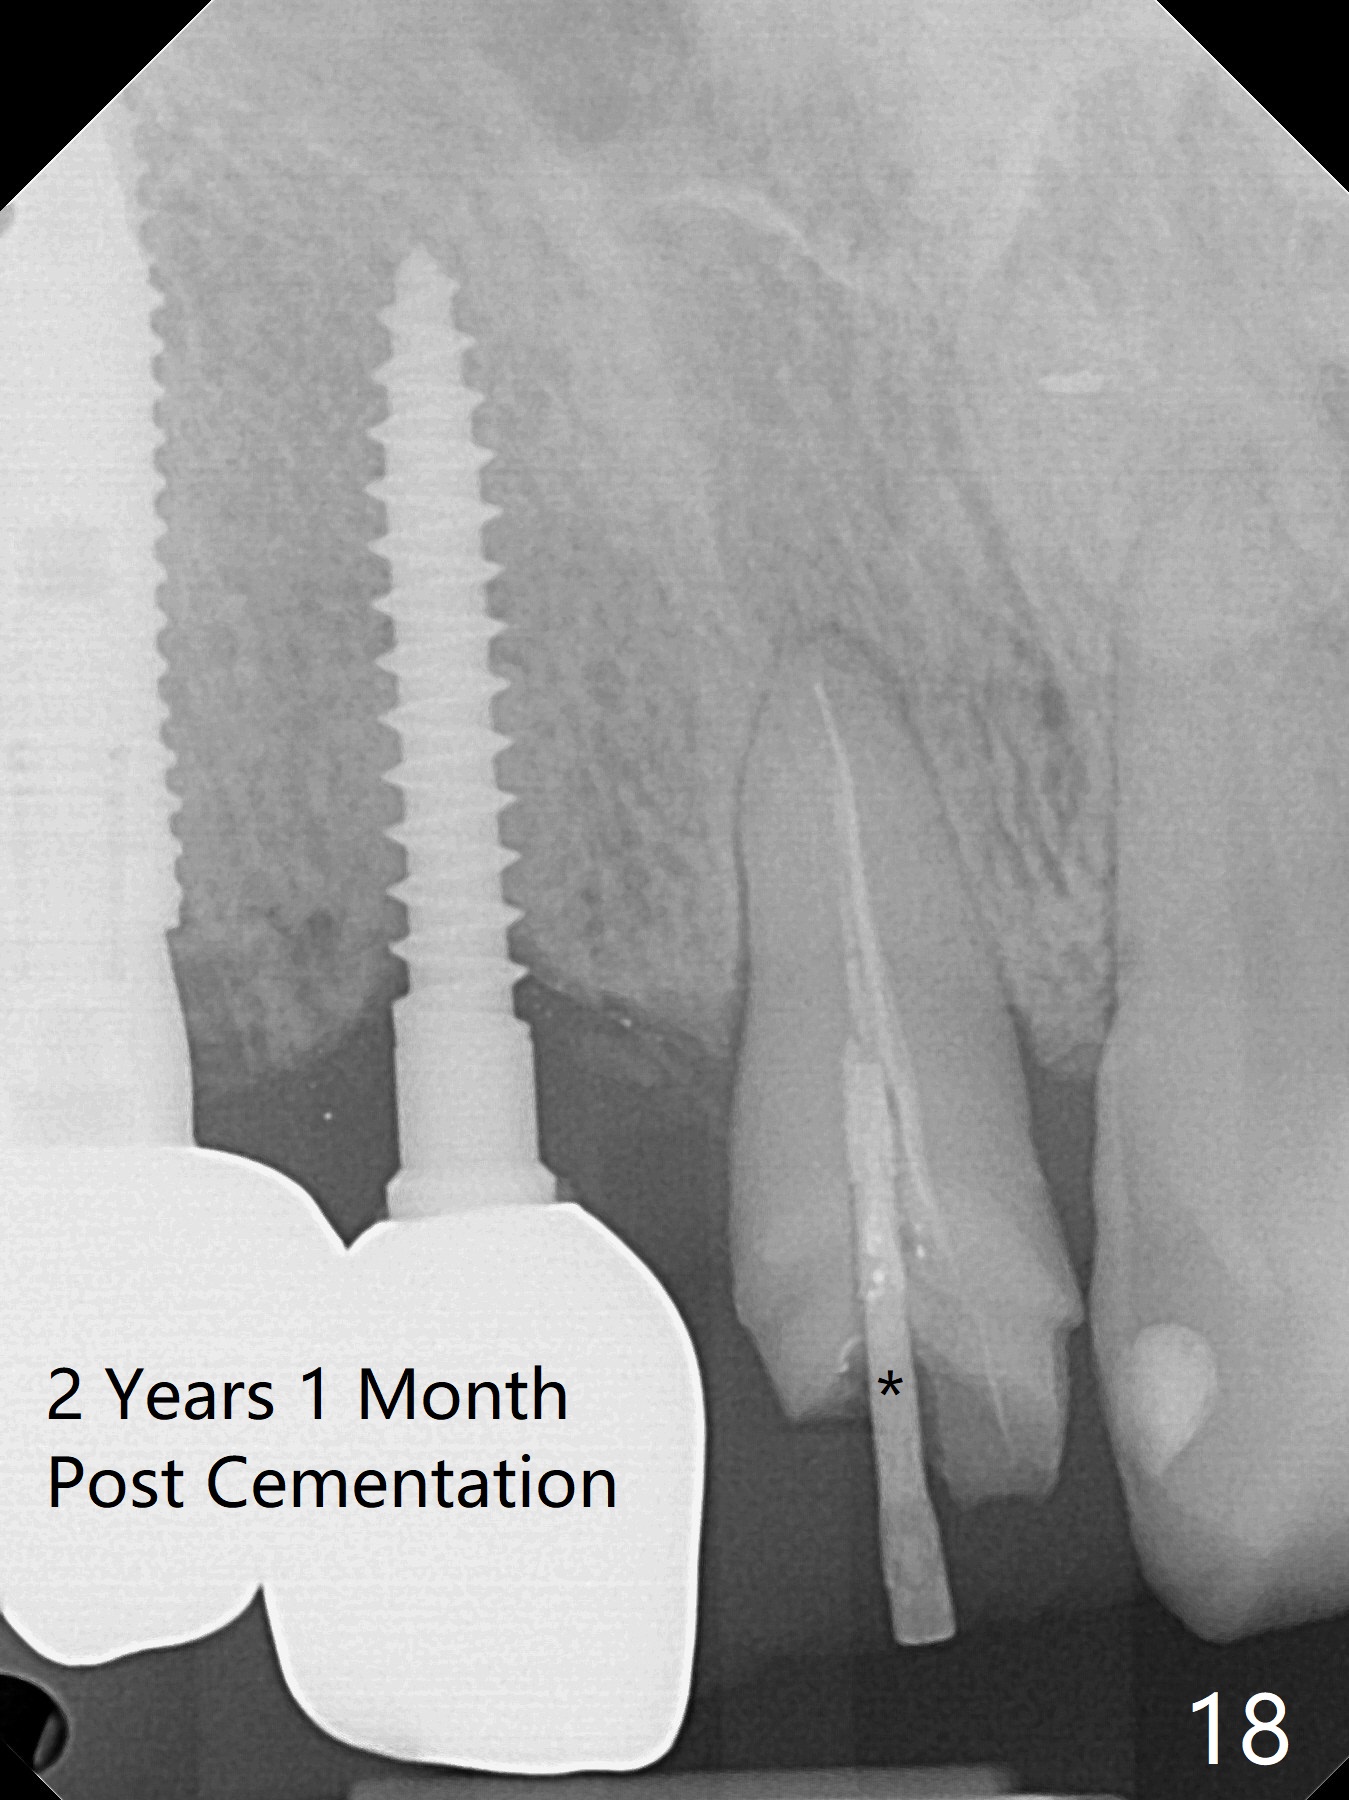

Since the ridge at #7 is ~ 4 mm, a 2.5x14 mm 1-piece implant is placed (Fig.8) after 1.2 mm (Fig.7), and 1.5 mm drills at 12 mm and 2 mm drill at 8 mm.  Later the implant is placed deeper (Fig.10).  There is no bone loss 7 or 12 months postop, respectively (Fig.11,12).  After Diode gingivectomy, there is papillary formation (Fig.13).  No provisional is provided after impression (with the abutment torqued at #6) for oral hygiene.  With access holes at #6 and 7, crowns are bonded with minimal residual cement (Fig.14 <, which is removed later).  There is no hard (Fig.15,16) or soft (Fig.17 *) atrophy 26 months postop, i.e., 13 months post cementation, due to the presence of socket shield (Fig.15 <, as compared to Fig.1).  In fact the tooth #8 has mobility and fremitus (short root/poor crown/root ratio, Fig.16); occlusal adjustment is done 13 months post cementation.  The crown is dislodged 2 years 1 month post cementation; a prefabricated post is being tried in (Fig.18).  There is no atrophy, bone loss or infection at #6 (with socket sheath (*)) or 7 two years 5 months post cementation (Fig.20-27).